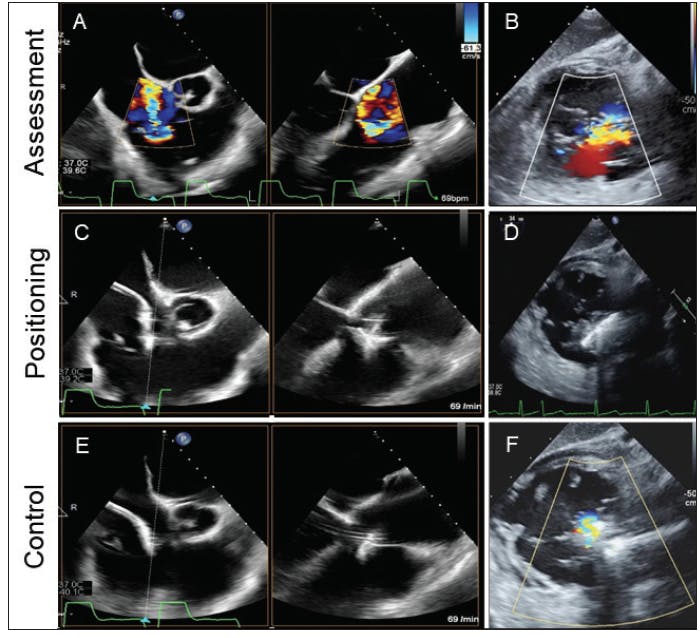

Intraprocedural imaging requirements vary depending on the TTVI approach. In edge-to-edge repair, intraprocedural TEE is crucial for visualizing the tricuspid valve leaflets and catheter positioning. The localization of the coaptation defect is best achieved by multiwindow imaging. Although three-dimensional echocardiography is useful to image and understand the tricuspid valve pathology, the limitations of spatial and, more importantly, temporal resolution need to be considered. The combination of a bicommissural view with the corresponding orthogonal x-plane view, resulting in a “grasping view” and a transgastric view, is best suited for deciding on procedural strategy but also to guide through tricuspid valve edge-to-edge repair (Figure 1A-1D). After clip deployment, adequate grasping of leaflet tissue (Figure 1E) and the extent of TR reduction (Figure 1F) should be confirmed again using a multiwindow approach.13

Figure 1. Intraprocedural imaging during edge-to-edge repair for TR. Using a bicommissural view with an orthogonal x-plane to visualize a modified “grasping view” (A) is necessary for edge-to-edge repair and might help in TR assessment. A transgastric view (B) is helpful to visualize the main regurgitation jet. Both the bicommissural x-plane view (C) and a transgastric view (D) can be used to guide clip positioning and leaflet grasping. Safe positioning of the deployed clip is visualized (E), and the remaining regurgitation is assessed by a transgastric view (F).